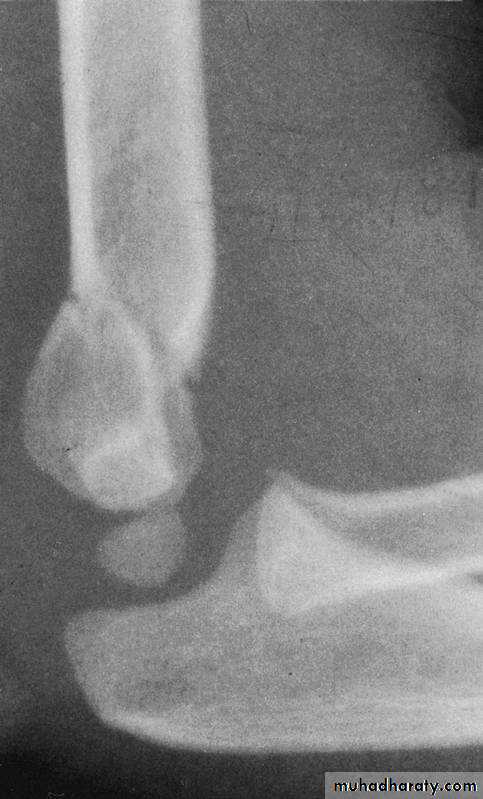

This fracture

was irreducibleby closed

manipulation.

Injury film